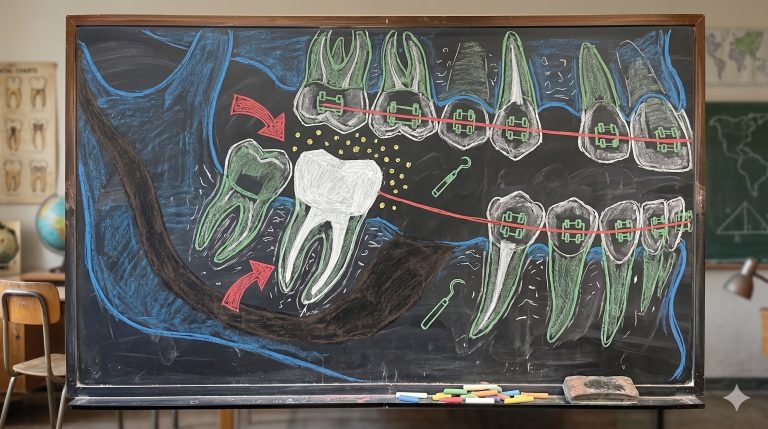

Incisivos Impactados: Minimizando el Riesgo de Recidiva Vertical y Discrepancias Gingivales

La importancia de la intervención temprana para evitar problemas como el desplazamiento de la línea media, la pérdida de … [Leer más...] acerca de Incisivos Impactados: Minimizando el Riesgo de Recidiva Vertical y Discrepancias Gingivales

Consideraciones Clínicas para la Tracción de Múltiples Incisivos y Caninos Maxilares Impactados

artículo que compartimos el día de hoy se llama Cone-beam CT evaluation of orthodontic treatment outcomes for multiple … [Leer más...] acerca de Consideraciones Clínicas para la Tracción de Múltiples Incisivos y Caninos Maxilares Impactados